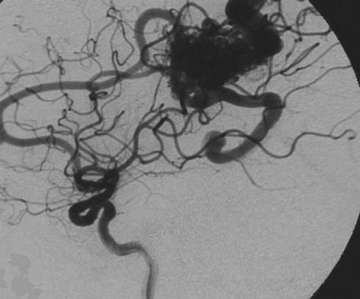

Many patients with AVMs have no symptoms. Some patients may have seizures or persistent headaches related to the AVM. However, most AVMs, as stated above, come to attention due to bleeding. This bleeding in the brain causes a severe headache that is rather sudden in onset and is typically associated with nausea and vomiting. Patients with bleeding in the brain may also lose consciousness. Patient with bleeding is evaluated typically with a CT scan. Once bleeding is confirmed on a CT scan, definitive diagnosis of an AVM is made by angiography. Figure 3 shows the typical appearance of an AVM on angiography. MRI is also very helpful particularly with localizing the AVM. Once the location and appearance of the AVM is decided, definitive plans for treatment are made.

Figure 3. The AVM is seen as a dense collection of vessels (the nidus) that connect the arteries directly to the veins without an intervening capillary system. Next is a picture depicting approximate location of this AVM in the brain. Red arteries bring oxygenated, high pressure blood to the AVM nidus. Blue veins drain blood from the AVM. Arrows indicate direction of the blood flow.